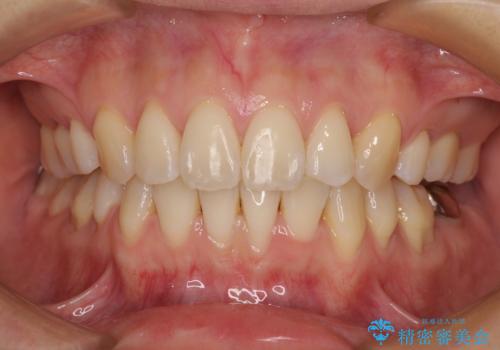

乱れた咬み合わせを治したい 全顎補綴治療

インプラントにより奥歯の咬み合わせを安定させ、歯周外科処置などにより歯肉の状態を改善させながら、オールセラミッククラウンにて全顎補綴治療を行うこととしました。

咬む力が強いため、治療の途中で仮歯が外れたり、割れてしまったりと、治療は難航しましたが、奥歯のインプラントが機能し始めた頃から徐々に咬み合わせが落ち着き、前歯も自然な外見のオールセラミッククラウンにて仕上げることができました。

長いこと悩んでいた顎関節の痛みも改善され、患者様には大変満足していただきました。